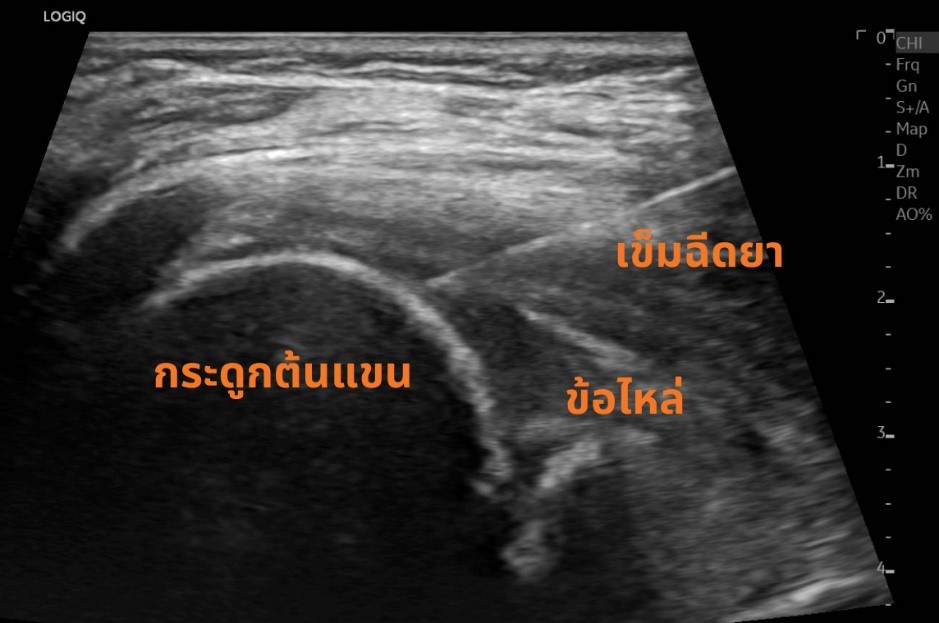

การรักษา หากอาการไม่มาก สามารถใช้การทำกายภาพบำบัด ออกกำลังกาย ร่วมกับเครื่องมือทำกายภาพ เพื่อเพิ่มพิสัยการขยับของข้อให้ได้มากขึ้น และหากอาการรุนแรง ที่ VASU pain management เรามีวิธีการรักษาโดยใช้การฉีดกลูโคสเข้าไปบริเวณข้อไหล่ และเส้นเอ็น เพื่อทำให้ผังผืดที่ติดนั้นคลายออก (Hydro dissection) ซึ่งการทำหัตถการนี้จะใช้อัลตราซาวน์ในการนำทางของเข็ม ทำให้เราสามารถระบุตำแหน่งได้ชัดเจน ปลอดภัย และมีประสิทธิภาพมากยิ่งขึ้น โดยหากใช้วิธีดังกล่าว จะสามารถทำให้ผู้ป่วยหายจากภาวะไหล่ติดได้เร็วมากยิ่งขึ้น